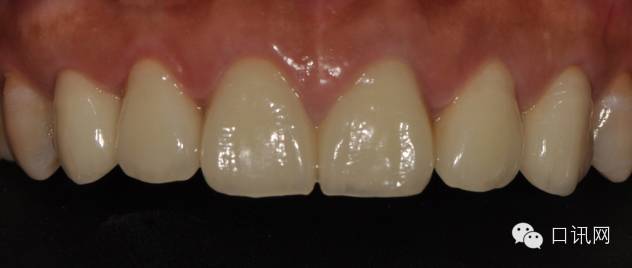

患者发F音以及下嘴唇干湿线的位置

修复体完成口内照片

/>